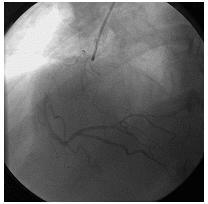

第二次手术过程

手术时间: 2015年7月19日。

术中用药:术中追加肝素4000单位。

手术过程:BMW导丝通过LAD近中段闭塞病变处至远端,送入抽吸导管,抽吸血栓后可见全程显影,注入替罗非班,用PWR球囊2.0×15 mm用8-12 atm×10 s×2次扩张,用Voyager球囊2.0×15 mm用8-12 atm×10 s×2次扩张,选Execel支架2.5×36 mm植入LAD中段病变用12 atm×10 s×1次扩张,再用NC 球囊2.75×15 mm×12-22 atm×10 s×4次扩张,用Grip球囊3.0 mm×12 mm用12 atm×10 s×4次扩张。造影示未见残余狭窄,TIMI血流3级。

![]()